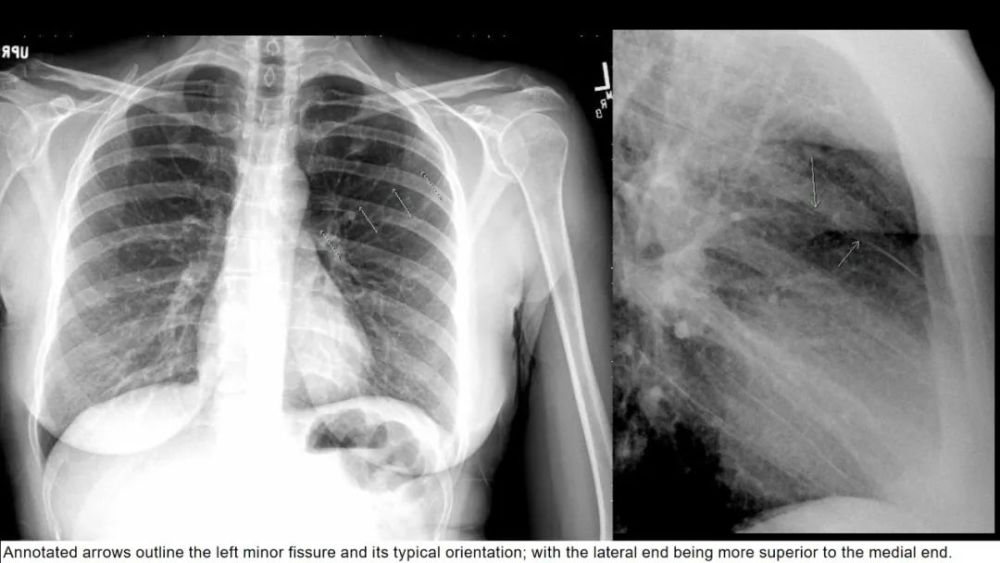

左侧水平裂

Left minor fissure

CT上的检出率为:8% , AP胸片为1.6%

左侧水平裂将舌叶从下叶其它部分分隔出来 舌叶仍然保留其上段和下段 , 不同于右肺中叶 内侧段和外侧段 , 因此左肺的段解剖保持完整